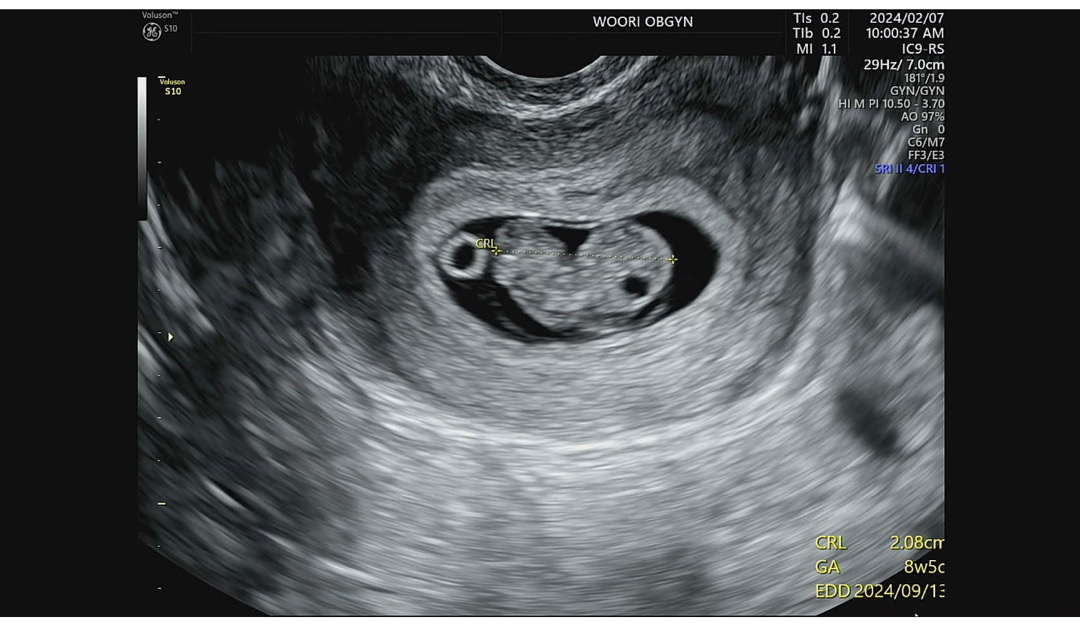

8주 5일 초음파에 도치맘 확정이에요

아직 2센치 쪼꼬미지만 머리도 동그랗고 뭔가 기특해요ㅠㅠㅠㅠㅠ 단축근무는 커녕 4주부터 쭉 밤 10시까지 야근하고 그랬는데 잘 커서 예쁘네요🥲